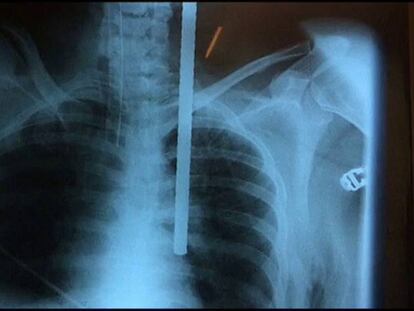

La niña tropezó en la azotea e iba a caer al vacío cuando su abuela la abrazó y ambas cayeron. La pequeña resultó ilesa y la mujer impactó con el hierro